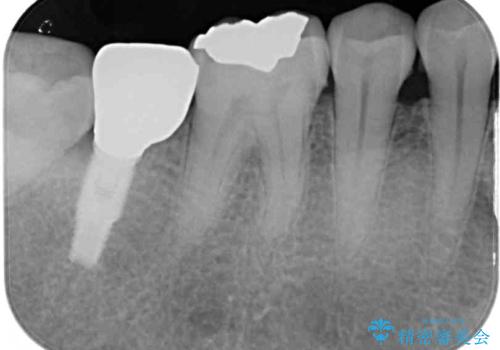

ゴールドインレーは銀歯のインレーやセラミックインレーと比べ、「技工操作の精度が高く、適合が著しく良い」というメリットがあります。特に上の奥歯は歯科医師の操作が行いにくいため、「適合の良さ」は再治療のリスクを防ぐ上でとても重要な要素となります。

上の奥歯は金属色が見えることもないため、審美的な問題は全くありません。

咬み心地はとても良好で、全く違和感がなく、患者様には大変満足していただきました。